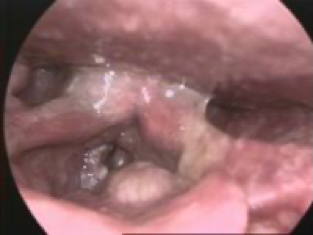

- Warty epithelial growths, typically on the vocal cords

- May extend into the trachea

- Laryngoscopy: Direct visualisation of vocal lesions